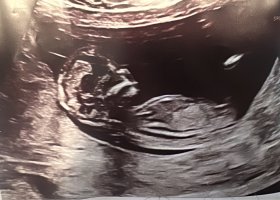

Vil dere gjette ut fra teorien hva kjønnet kan være? blir litt gal og sykehuset ville ikke si det fordi det var for tidlig..

nå har jeg fått bekreftet om at det er liten jenteHar disse ogsåhåper man kan se det på et av bildene hvertfall (alle de er tatt samme dag 12+3) @lyse gul